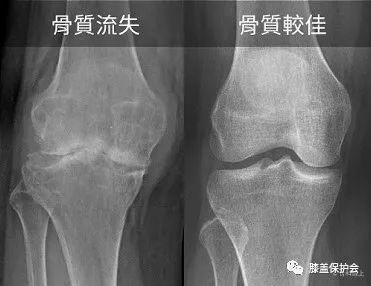

骨质增生x光片图解,骨质增生图解

会产生很厉害的骨质流失,对比退化性膝关节炎的病患,x光可观察到 骨头

另外,我们可以发现很多向鸟嘴一样的刺,这是所谓的骨质增生.